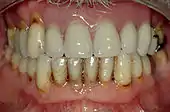

Abrasão dentária é a perda da estrutura dentária por forças mecânicas externas. Uma vez que a abrasão ultrapasse o esmalte dos dentes, são rapidamente destruídas estruturas da dentina e do cemento.

Esta patologia por pode ser causada pelo uso de escovas de dente, palitos, fio dental. Sua aparência é comumente descrita em forma de V, ( o que não permite o contato da escova dentária com a base do defeito). Os dentes mais comumente afetados são pré-molares e caninos.